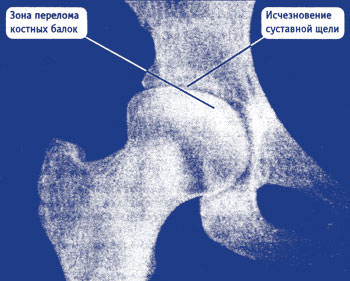

На этом снимке видно, что суставная щель уменьшилась, и головка сустава начала деформироваться. В этом случае диагностируется сустав. Но, если пациент попадает к плохому врачу с симптомами, похожими на проблемы с позвоночником, то настоящее заболевание могут не найти. Ведь признаки коксартроза могут быть схожими с остеохондрозом.

На снимке можно увидеть большое поражение хряща, суставная щель почти исчезла. Сустав довольно сильно деформирован, что означает прогрессирование болезни. В случае таких разрушений чаще всего назначается замена сустава.